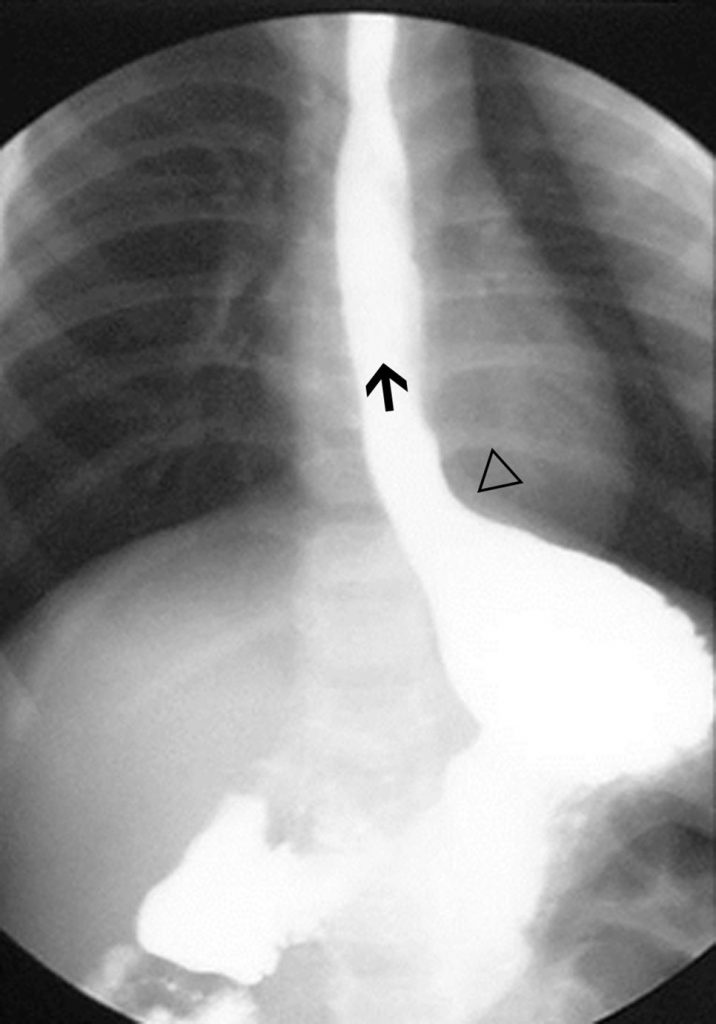

Le transit œsogastroduodénal va montrer en scopie une remontée de l’estomac vers l’œsophage du produit de contraste baryté préalablement ingéré par l’enfant (par sonde œsophagienne, biberon ou verre suivant l’âge de l’enfant) (figure 13.1). La visualisation du reflux n’est pas constante et le fait de ne pas en voir n’élimine pas le diagnostic.

Fig. 13.1 Reflux gastro-œsophagien chez un nourrisson avec une malrotation intestinale.

Reflux massif du produit de contraste baryté mis en place dans l’estomac par une sonde nasogastrique retirée après le remplissage. Le cardia (flèche) est béant. L’incisure du cardia (angle de His) (tête de flèche) est très ouverte.

L’importance du reflux (en volume et en hauteur dans l’œsophage) est notée.

Des anomalies anatomiques peuvent être associées : ouverture de l’angle entre l’œsophage et la grosse tubérosité gastrique (incisure du cardia ou angle de His), béance du cardia.